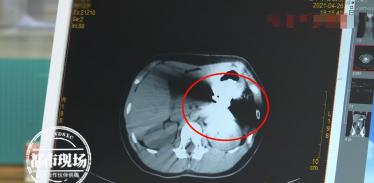

来到医院后,医生立马给小朋友做CT,检查发现,这个异物是一把已经锁上的挂锁,要想取出不是那么容易,好在就医及时,内脏没有造成损伤。